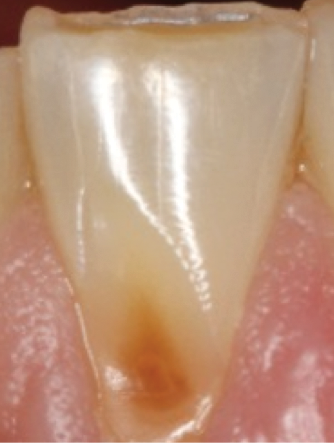

Concavities on the lingual surfaces of maxillary incisors (Figure 5) or occlusal surfaces of premolars and molars (Figure 6) with hollowed areas are signs of dental erosion that may be combined with attrition. Gastric acid is the most common cause of erosion on the lingual aspects of teeth. The most frequent etiology of gastric acid attack is the clinical diagnosis of GERD.13 Patients with anorexia nervosa and bulimia nervosa exhibit higher incidences of dental erosion.29 In Figure 7, a schematic drawing of an upper incisor demonstrates the sequence of loss of dentin and enamel on the lingual/palatal aspect. The direct contact of acid on the tooth structure is the main mechanism as the inorganic material dissolves, leading to a loss of surface hardness.13

Fig 5. Lingual erosion due to bulimia.

Figure 5